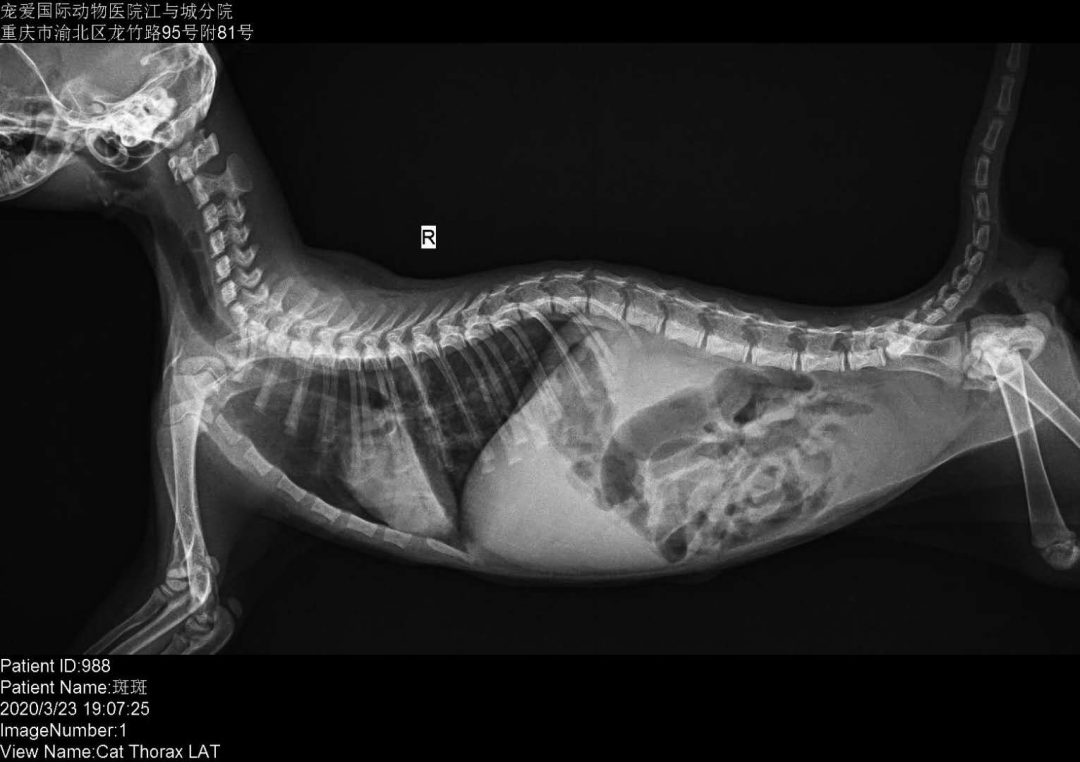

猫肺炎x光图片,肺炎x光图片

猫咪吞食奶嘴残片后家长自行催吐,引发「异物性肺炎」

盘点10张不可思议的猫咪x光片,真相令人后怕!

胸膜肺炎--慢性气胸_猫博士_新浪博客

肺炎x光图片

猫传腹x光图片

猫腹水x光图片

猫x光图片解析

正常猫肺部x光片

猫腹水x光图片解析

猫x光图片解析腹部

猫x光片解读健康猫

猫传腹x光片

猫x光

猫咪X光片